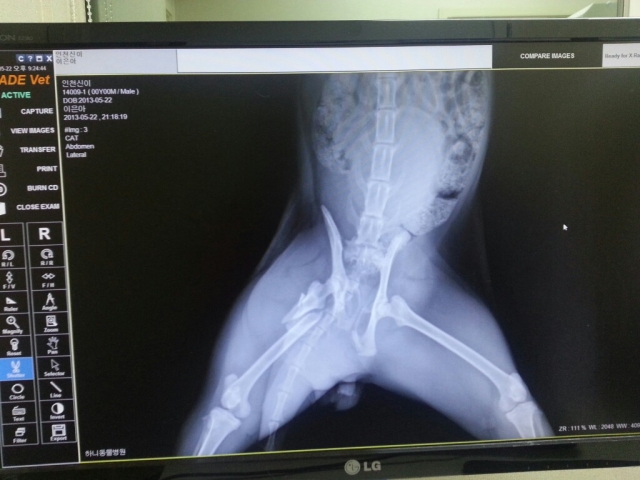

목동협력병원으로 옮긴후 정밀검사와 엑스레이를 다시 찍었습니다.

정밀검사와 엑스레이 판독후 원장님께서 수술...해보자십니다....

압박배뇨로 임상실험까지 해보시고 핀을 박을 위치며 이것저것 자세한 설명과 따뜻한 위로까지...